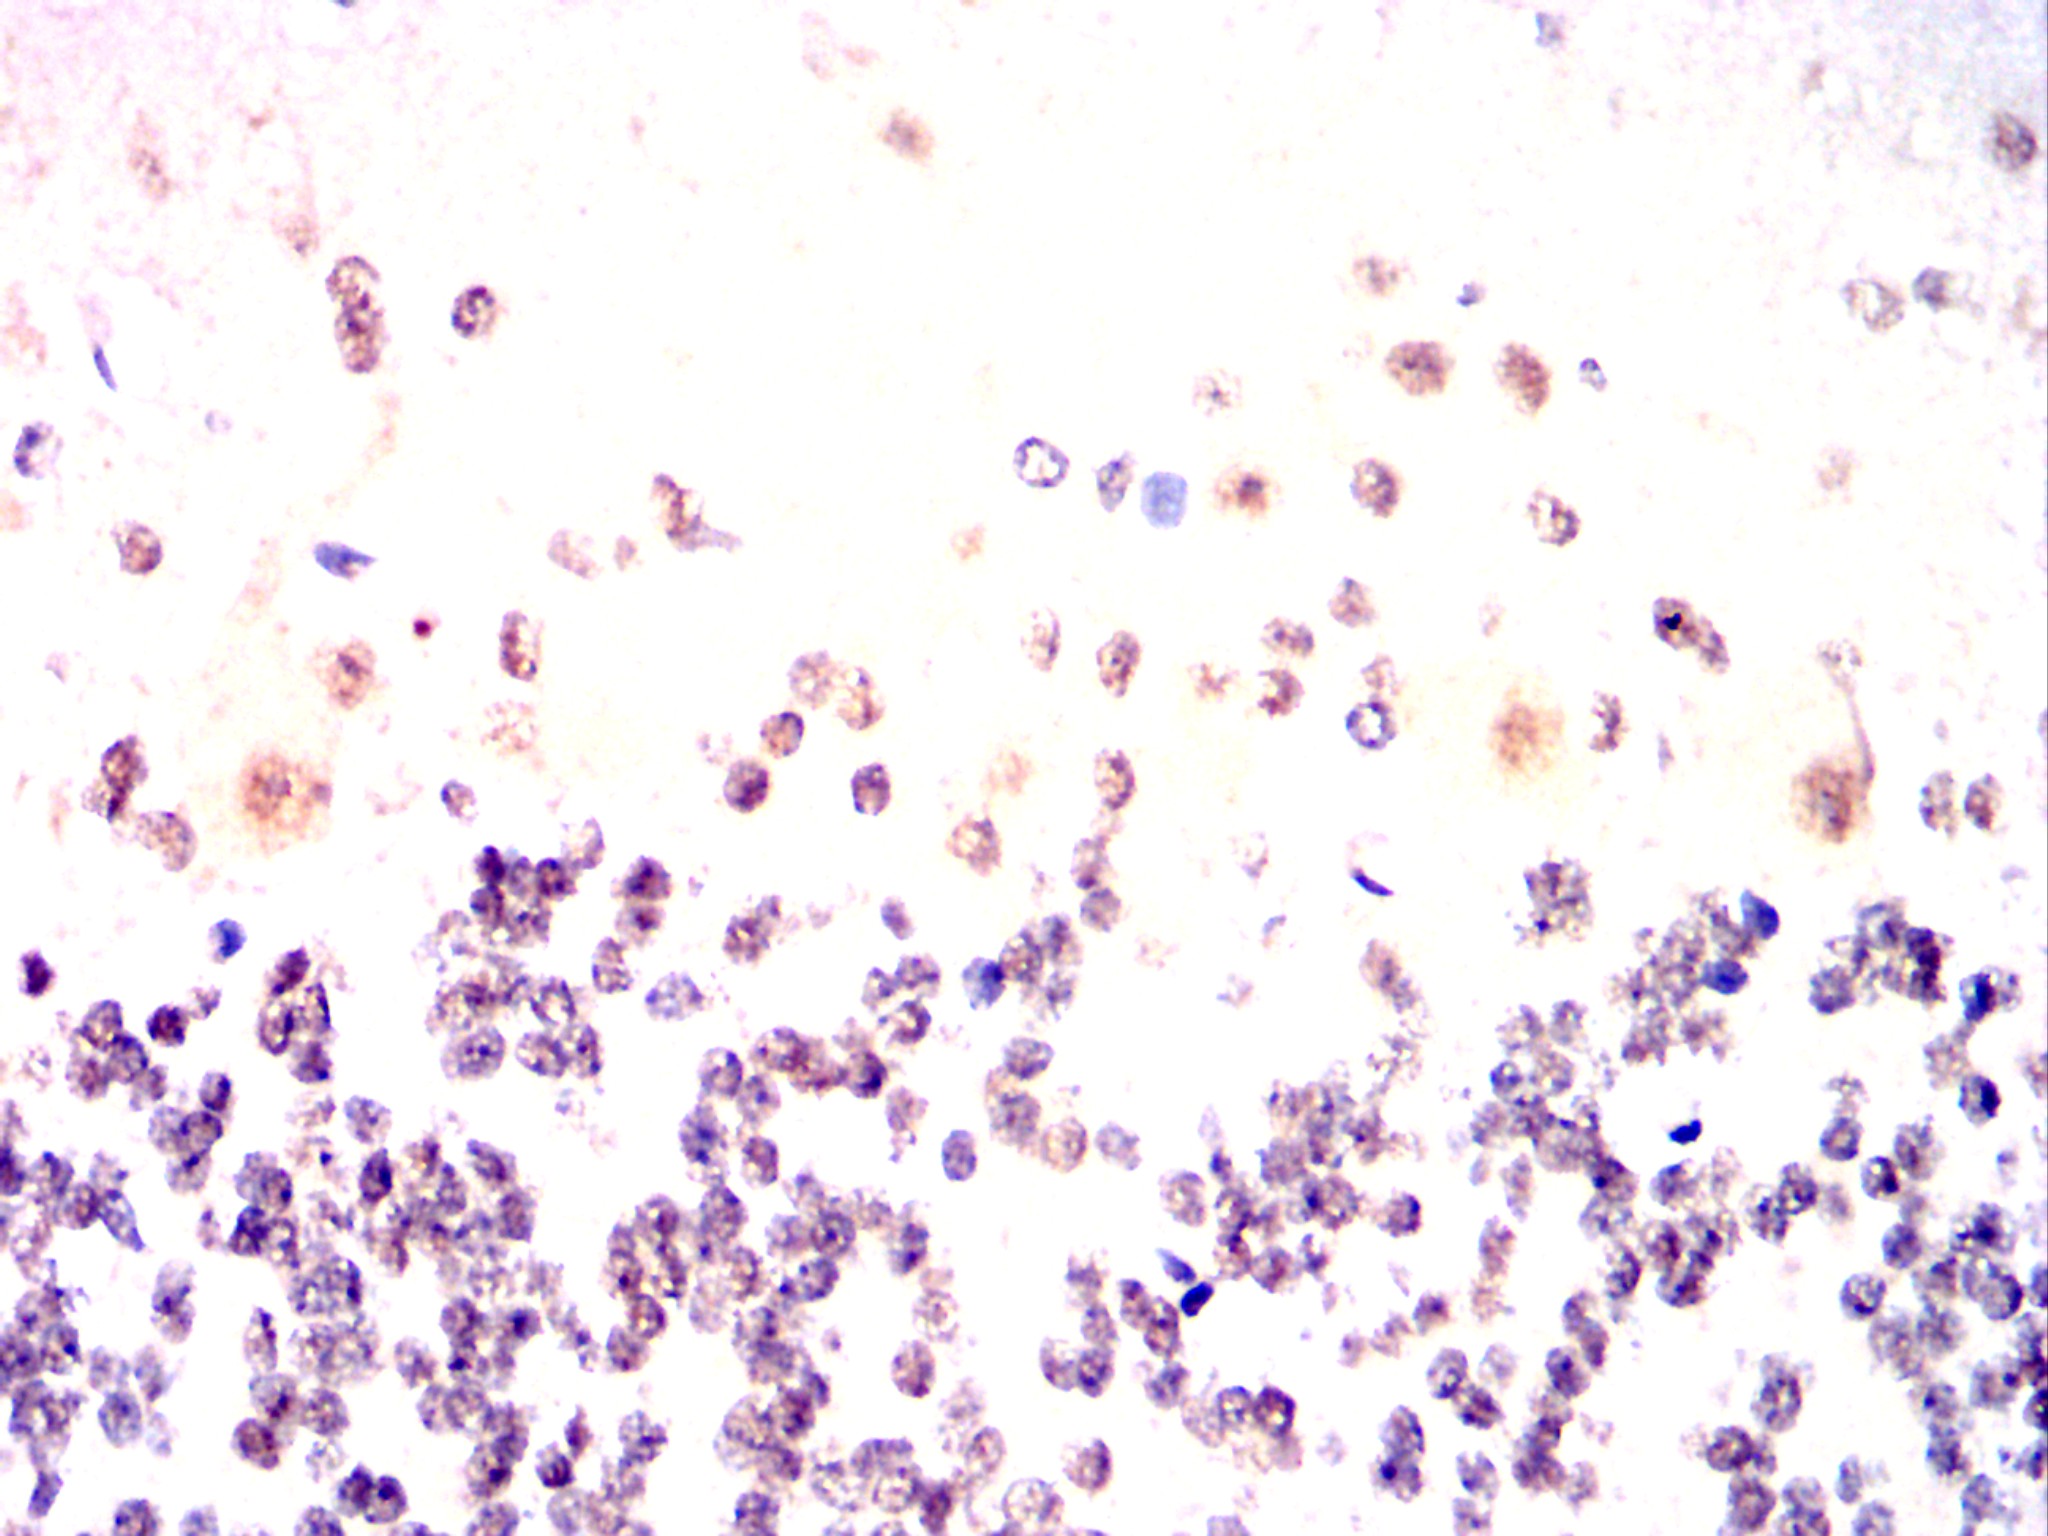

Immunohistochemical analysis of paraffin-embedded human esophageal cancer tissues using P2RX7 mouse mAb with DAB staining.